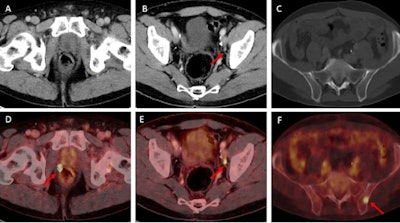

Examples of individual minor and major therapeutic change in patients with biochemical recurrence after radical prostatectomy undergoing F-18 rhPSMA 7.3 PET/CT examination.

(A, D) 70-year-old patient (PSA = 0.49 ng/mL) with F-18 rhPSMA 7.3 ligand uptake in the right prostatic bed (B, red arrow) without clear morphological correlate on corresponding CT. Therapeutic management was changed from radiation therapy of the prostatic bed to radiation therapy of the prostatic bed with simultaneous integrated boost being considered a minor change.

(B, E) 57-year-old patient presenting with biochemical recurrence (PSA = 1.0 ng/mL) seven years after radical prostatectomy. Fused F-18 rhPSMA 7.3 PET/CT shows focal PSMA ligand uptake in an unsuspicious lymph node adjacent to the left external iliac artery suspicious for singular lymph node metastasis. Therapeutic management was changed from radiation therapy of the prostatic bed and additional short-term androgen deprivation therapy to salvage lymphadenectomy.

(C, F) 62-year-old patient presenting with biochemical recurrence (PSA = 0.3 ng/mL) a year and a half after radical prostatectomy. Fused F-18 rhPSMA 7.3 PET/CT shows focal PSMA ligand uptake in the left iliac bone without unequivocal morphological correlate. Therapeutic management was considered a major change (change from androgen deprivation therapy to stereotactic body radiation therapy of the singular bone metastasis). Images courtesy of the JNM.